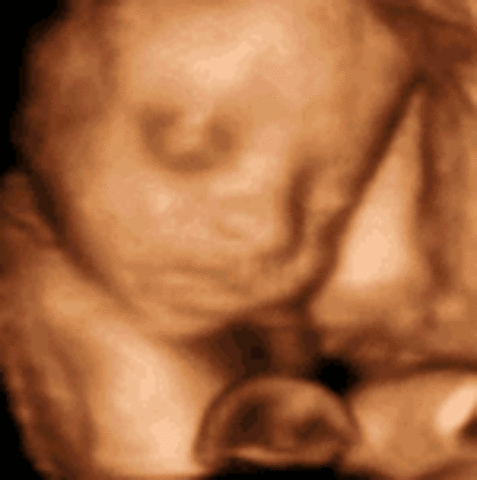

• Week 28

Week 28

Hair is visible through 4D ultrasounds. Milk teeth have started growing under the gums and eyes start to move.